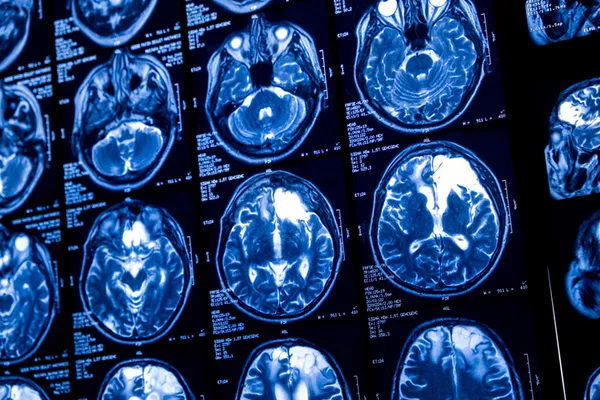

80'li ve 90'lı yaşlarına iyi bir hafızayla gelen insanların, akranlarına göre daha fazla yeni beyin hücresi üretme eğiliminde olduğu ortaya çıktı. Independent Türkçe'ye göre; Illinois Üniversitesi Tıp Fakültesi araştırmacıları, ilerleyen yaşlarda çok az yeni sinir hücresi üreten Alzheimer hastası akranlarına kıyasla, bu "süper yaşlılar"ın beyinlerinin daha verimli olduğunu belirtiyor.

Sinir hücreleri, insanların neredeyse tüm fonksiyonlarını destekler. Hafıza merkezi hipokampus gibi bazı beyin bölgelerinde, kişinin yaşamı boyunca yeni nöronlar üretilir. Primatlar üzerinde yapılan araştırmalar, sinir hücresi gelişiminin ilerleyen yaşlarda daha güçlü hafızayla bağlantılı olduğunu daha önce göstermişti. Yeni araştırma, bu tür bir nörojenezin insanlarda da meydana geldiğini ortaya koyuyor. Yeni araştırmada 5 farklı gruptan bağışlanan beyin örnekleri analiz edildi: Süper yaşlıların beyinleri, "olağanüstü hafıza becerileri" olduğu kanıtlanmış 80 yaş ve üstü bağışçılardan alındı.

Araştırmacılar, üç tür hipokampus hücresini inceledi: Nöronlara dönüşme potansiyeli olan kök hücreler, sinir hücrelerine dönüşme sürecindeki nöroblast adlı hücreler ve işlevsel sinir hücresi haline gelmeden hemen önceki olgunlaşmamış nöronlar.

Araştırmacılar süper yaşlıların, yaşıtlarına göre daha aktif bir şekilde yeni sinir hücreleri ürettiğini ve bunun da hafızalarının kendine özgü "dayanıklılığının işareti" olduğunu saptadı.

Dr. Lazarov, "Süper yaşlılardaki nörojenez oranı diğer sağlıklı yaşlı yetişkinlerin iki katıydı. Beyinlerindeki bir şey üstün bir hafızayı korumalarını sağlıyor. Hipokampal nörojenezinin bunun gizli bileşeni olduğuna inanıyorum ve veriler de bunu destekliyor" diyor.